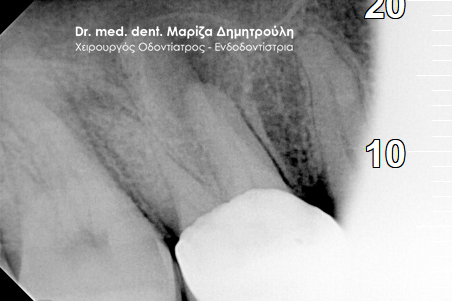

Η ασθενής προσήλθε με έντονο πόνο στο ιατρείο και είχε λάβει τις προηγούμενες μέρες αντιβίωση, εφόσον στην άνω αριστερή πλευρά της είχε οίδημα. Μετά την κλινική εξέταση διαπιστώθηκε η ύπαρξη ενός συριγγίου υπερώια μεταξύ των δύο άνω αριστερών γομφίων. Πραγματοποιήθηκε ακτινογραφία με την τοποθέτηση ενός κώνου γουταπέρκας για τη διάγνωση του υπαίτιου δοντιού, που είχε προκαλέσει την εμφάνιση του συριγγίου. Σύμφωνα με όσα αποκάλυψαν η κλινική και ακτινογραφική εξέταση ακολούθησε η έναρξη απονεύρωσης στο δεύτερο άνω αριστερό γομφίο, δεδομένου οτι είχε ένα βαθύ λευκό σφράγισμα ρητίνης που εκτεινόταν στο ύψος του νεύρου του δοντιού. Το δόντι είχε έντονα συμπτώματα πόνου κατά την επίκρουσή του.

Μετά την ολοκλήρωση της απονεύρωσης στο δεύτερο άνω αριστερό γομφίο το δόντι είναι ασυμπτωματικό. Η αποκατάσταση του δοντιού πραγματοποιήθηκε με λευκό σφράγισμα ρητίνης, εφόσον το έλλειμμα των οδοντικών ιστών ήταν μικρό και δε χρειαζόταν η προστασία του δοντιού με θήκη / στεφάνη δοντιού.

Σε δεύτερη φάση θα ακολουθήσει η επανάληψη απονεύρωσης στον πρώτο άνω αριστερό γομφίο, καθώς η απονεύρωση του δεν καλύπτει όλο το μήκος των ριζών του δοντιού και το δόντι μετά το πέρας της ενδοδοντικής θεραπείας συνεχίζει να πονά.

ΠΡΙΝ

ΜΕΤΑ